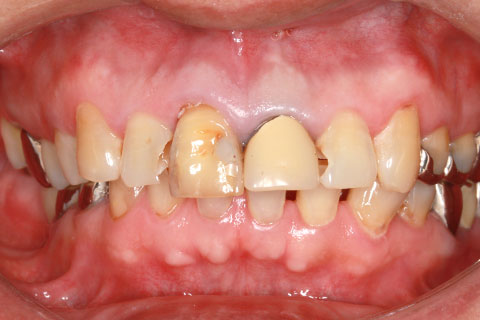

オールセラミックの症例1

上顎前歯のデコボコと色調を改善。

- 年齢・性別

- 40歳女性

- 治療期間

- 1ヶ月

- 抜歯

- なし

- 治療費

- 35.2万円

- 備考

- 前歯4本の変色歯及び歯列不正によるセラミック治療

- 治療内容

- 歯質を削除し、セラミック冠をセメント合着

- 施術の副作用(リスク)

- 知覚過敏、歯髄炎、荷重負担